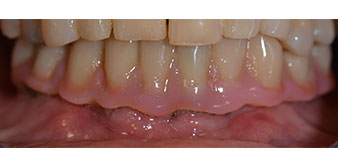

La paciente de 64 años se presentó con una dentición residual compuesta por las piezas dentales 38, 33 y 43 en el maxilar inferior y con una prótesis temporal fijada con ganchos en el maxilar inferior (figs. 1 y 2).

dentición residual

Fig. 1

Fig. 2

El tratamiento periodóntico necesario y la extracción de las piezas en el maxilar superior debía realizarse en un momento posterior, ya que la paciente es profesora y, en el momento de la consulta, estaba ocupada con los exámenes para las pruebas de acceso a la universidad. La paciente no podía comer ni hablar adecuadamente, ya que la prótesis temporal se rompía con mucha frecuencia y con una carga mínima.